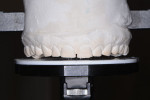

Space for maxillary anterior restorative materials was managed with increased tooth length, a change in vertical dimension, and the choice of restorative materials, thereby protecting the structural integrity of the teeth. A negative curve in the patient's maxillary posterior occlusal plane and the change in OVD provided sufficient interocclusal space for restorative materials on the maxillary posterior teeth (Figure 22).